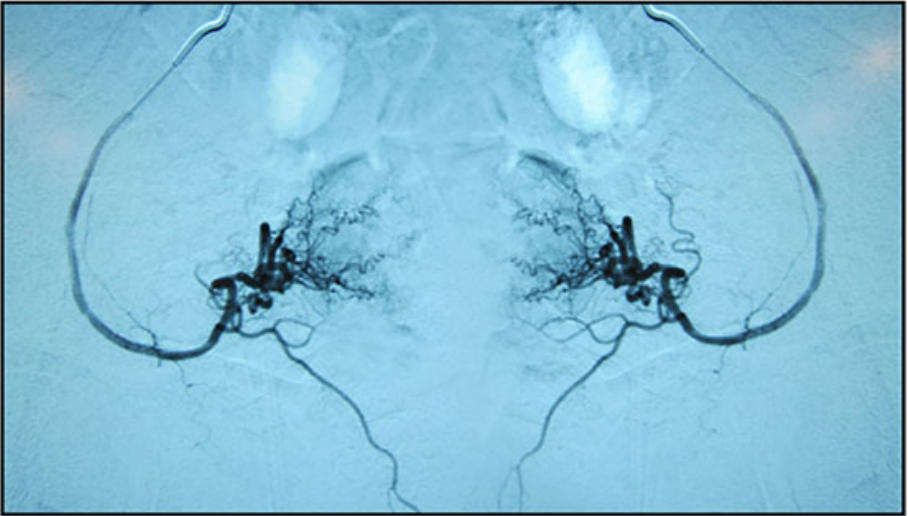

方 法:采用Seldinger技术经股总动脉入路,置入4F导管鞘,使用带血管造影弯曲的Terumo 0.035英寸导引导管插管至双侧髂内动脉,经此导管引入2.5F微导管至子宫动脉远端螺旋小动脉(下图),确认位置稳定后,经每条子宫动脉注入15 cm³细胞悬液(平均123.56*10⁶个细胞)。